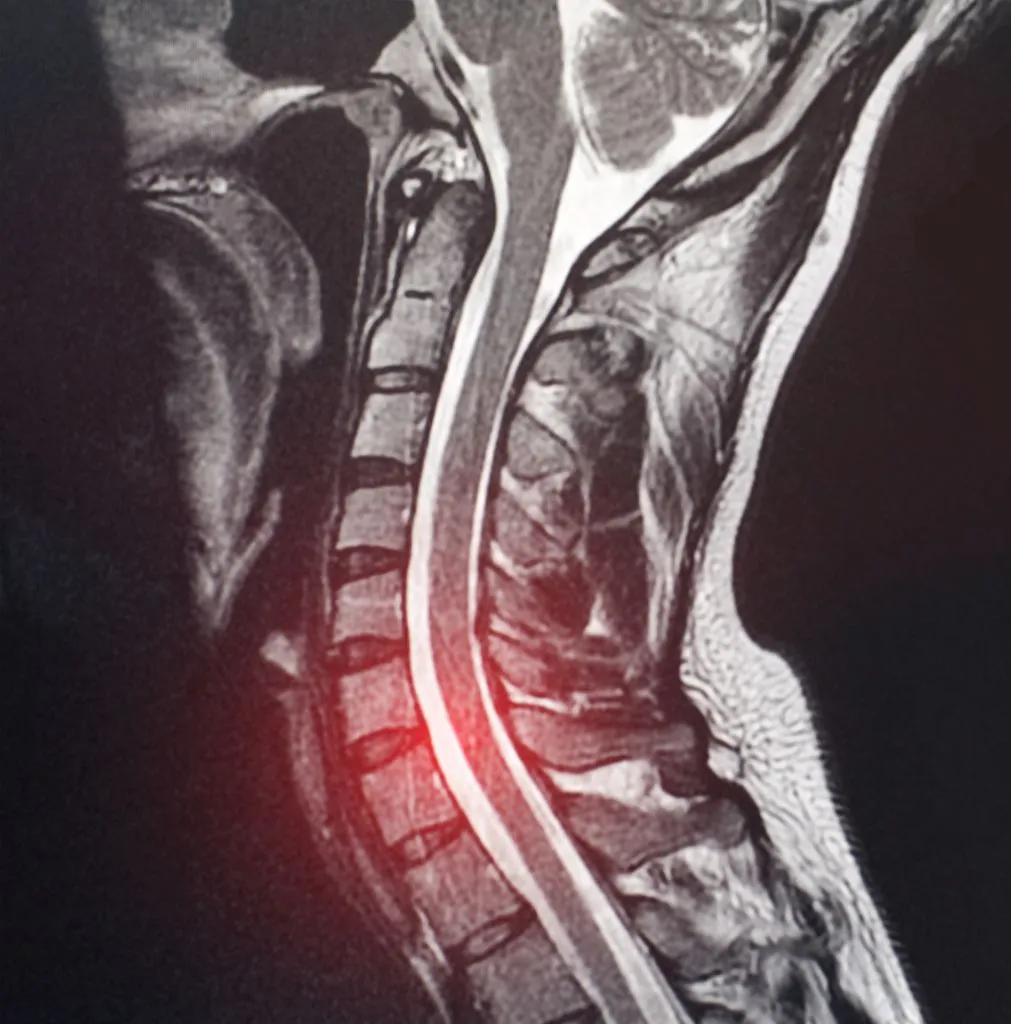

MRI: The gold standard for visualizing C7-T1 disc pathology. However, this level can be challenging to image due to shoulder overlap and the transition to the thoracic spine. Dedicated cervicothoracic junction sequences may be necessary for optimal visualization.

X-rays: While they cannot visualize the disc itself, flexion-extension x-rays can reveal instability at the C7-T1 level, which influences treatment decisions.

CT Myelography: Sometimes used when MRI is contraindicated or when bone detail is needed for surgical planning, particularly to assess foraminal narrowing from osteophytes.

Spine MRI image